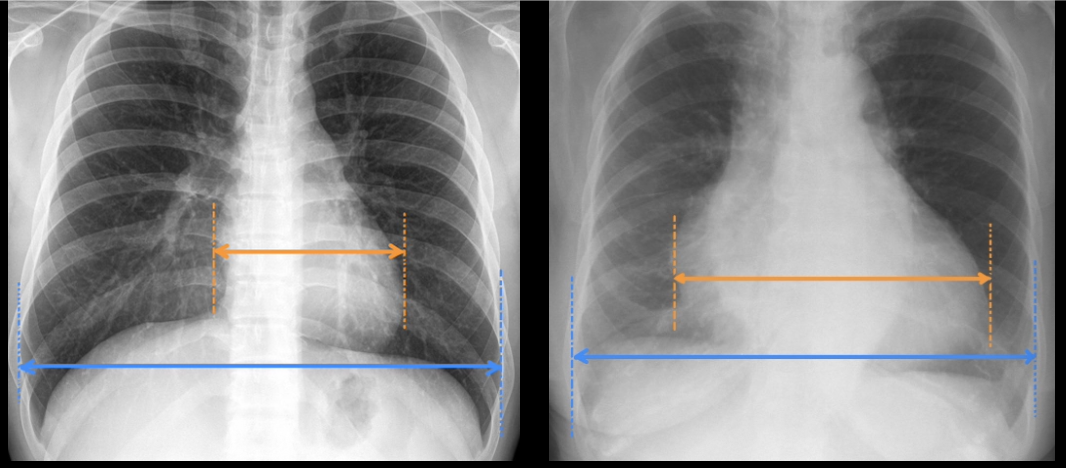

Pathology (in right image)?

Cardiomegaly